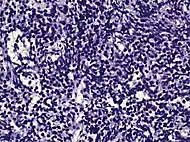

Intraductal carcinoma

Intraductal carcinoma of the prostate gland (IDCP), which is now categorised as a distinct entity by WHO 2016, includes two biologically distinct diseases. IDCP associated with invasive carcinoma (IDCP-inv) generally represents a growth pattern of invasive prostatic adenocarcinoma while the rarely encountered pure IDCP is a precursor of prostate cancer.[19] The diagnostic criterion of nuclear size at least 6 times normal is ambiguous as size could refer to either nuclear area or diameter. If area, then this criterion could be re-defined as nuclear diameter at least three times normal as it is difficult to visually compare area of nuclei.[19] It is also unclear whether IDCP could also include tumors with ductal morphology.[19] There is no consensus whether pure IDCP in needle biopsies should be managed with re-biopsy or radical therapy. A pragmatic approach would be to recommend radical therapy only for extensive pure IDCP that is morphologically unequivocal for high-grade prostate cancer.[19] Active surveillance is not appropriate when low-grade invasive cancer is associated with IDCP, as such patients usually have unsampled high-grade prostatic adenocarcinoma.[19] It is generally recommended that IDCP component of IDCP-inv should be included in tumor extent but not grade.[19] However, there are good arguments in favor of grading IDCP associated with invasive cancer.[19] WHO 2016 recommends that IDCP should not be graded, but it is unclear whether this applies to both pure IDCP and IDCP-inv.[19]

Intraductal carcinoma of the prostate with an infiltrative growth pattern may be morphologically difficult to distinguish from invasive cancer. One focus shows comedonecrosis (arrow), morphologically suggesting Gleason pattern 5 invasive carcinoma (a haematoxylin and eosin, b CK5/6)[19]

Intraductal carcinoma of the prostate with very patchy basal cells identified by immunohistochemistry. At least some of the glands lacking basal cell immunoreactivity represent intraductal rather than invasive carcinoma (a haematoxylin and eosin, b CK 5/6)[19]